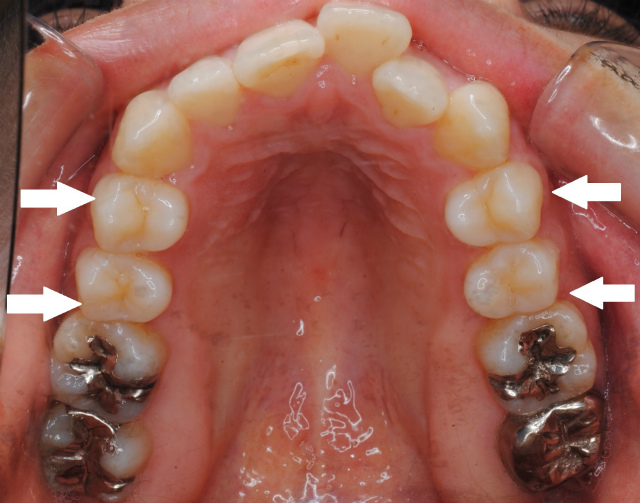

舌の側面が臼歯に被さって歯並びに作用してしまう。左側臼歯が前方に傾斜している様子